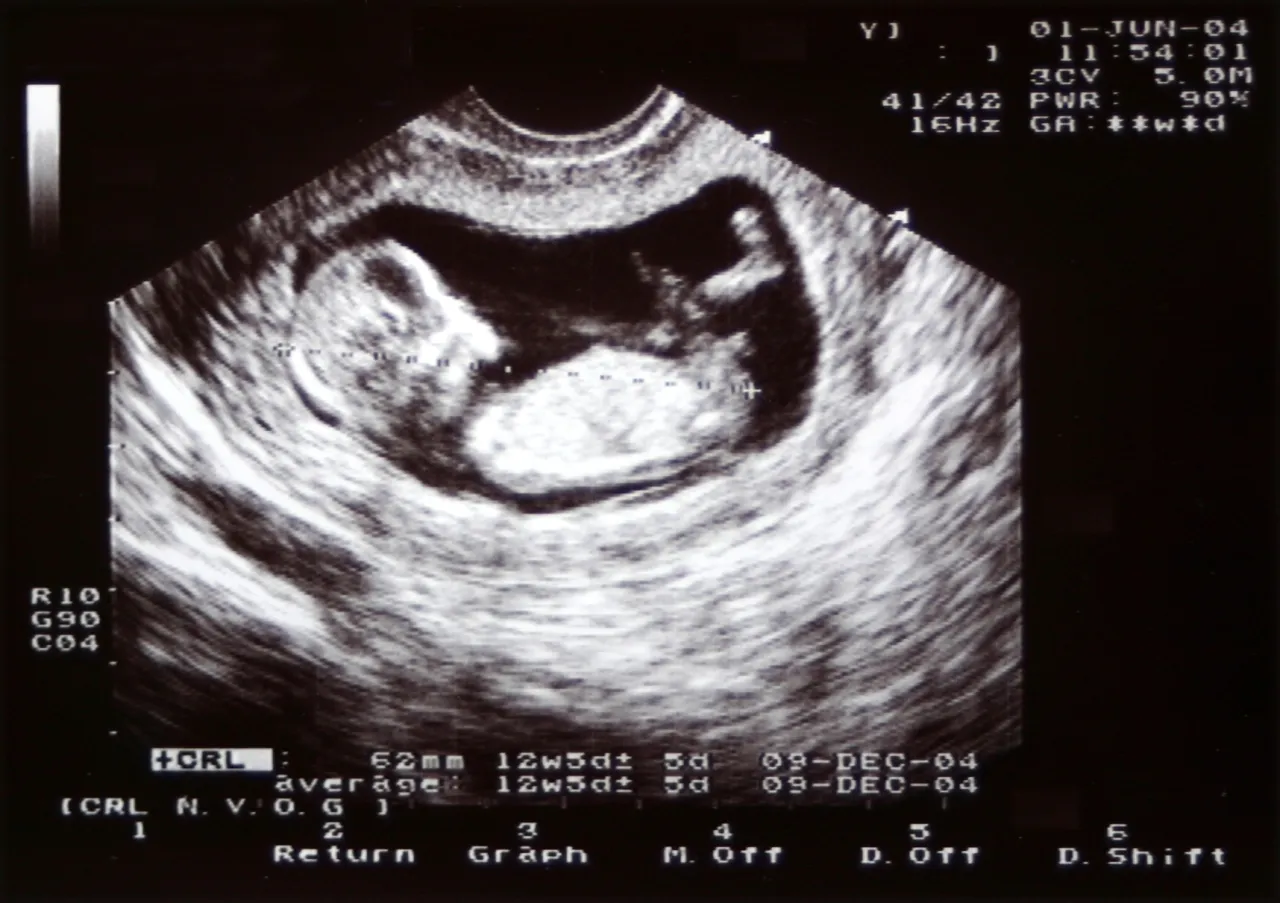

USG genetyczne I trymestru: dlaczego to badanie jest tak ważne?

Między 11. a 14. tygodniem ciąży wykonuje się kluczowe badanie, jakim jest USG genetyczne I trymestru (często nazywane po prostu USG I trymestru). To nie jest zwykłe USG! Podczas tego badania lekarz bardzo dokładnie ocenia rozwój płodu, zwracając uwagę na konkretne markery, które mogą wskazywać na zwiększone ryzyko wystąpienia wad genetycznych. Oceniane są między innymi:

- Przezierność karkowa (NT nuchal translucency): Pomiar płynu pod skórą na karku dziecka.

- Obecność kości nosowej (NB nasal bone): Jej brak lub nieprawidłowy rozwój może być markerem.

- Przepływ krwi w przewodzie żylnym i zastawce trójdzielnej serca.

Na podstawie tych pomiarów oraz Twojego wieku i wyników badań krwi, lekarz jest w stanie oszacować ryzyko wystąpienia wad genetycznych, takich jak zespół Downa, zespół Edwardsa czy zespół Patau. To badanie jest niezwykle ważne i pozwala na wczesne wykrycie ewentualnych nieprawidłowości, co daje czas na podjęcie dalszych decyzji i zaplanowanie odpowiedniej opieki.